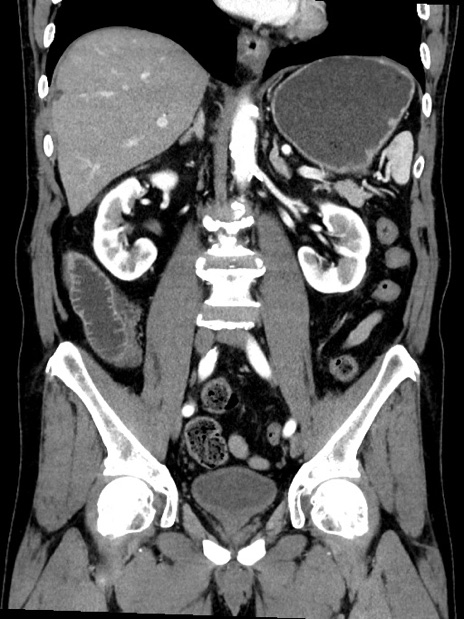

症例35(冠状断像)

【症例】70歳代 男性

【主訴】腹部膨満、嘔吐

【現病歴】昨日より腹部膨満感出現。本日増悪し、仙痛出現。嘔吐あり、受診。

【既往歴】糖尿病、胆摘後

【身体所見】BP 149/80mmHg、HR 74/min、BT 35.9℃、腹部:膨満、軟、圧痛なし。腸雑音減弱あり。上腹部正中切開瘢痕あり。

【データ】WBC 13500、CRP 1.72